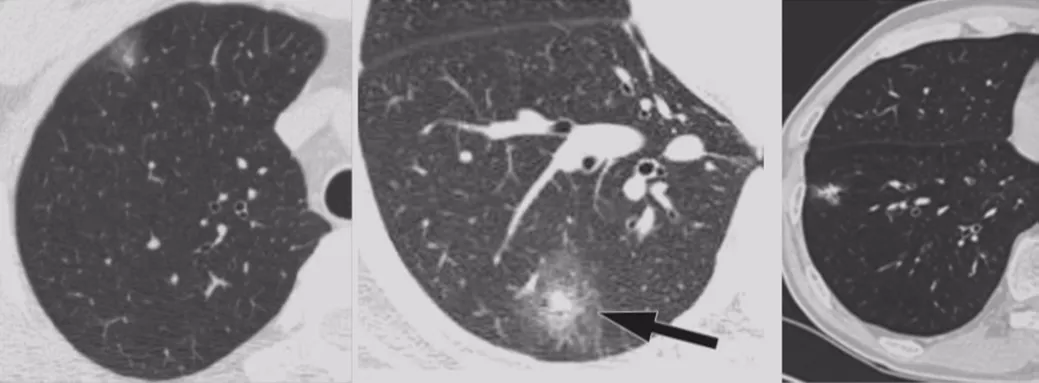

局灶性机化性肺炎

机化性肺炎有一个特点,它会有动态变化,大小和形态都有很大的变异,形态不规则呈多角形,贴近胸膜面(可有局限性胸腔积液)或沿支气管血管束分布,有粗长毛刺、尖角、向心性弓形凹陷、支气管扩张,部分病灶中心可出现低密度区(增强时呈周围强化),部分病灶边缘可见肺泡隔增厚而使边缘清晰,纵膈、肺门淋巴结增大较少见。

多灶性COP

多灶性机化性肺炎也可以表现为胸膜下或支气管周围的磨玻璃密度片影伴实变,支气管或细支气管周围边界不清的磨玻璃密度小结节,大的结节和肿块,反Halo征。因此,大家在做肺结节鉴别诊断的时候一定要考虑到该疾病。

BOOP

双肺多发的磨玻璃影或斑片实变影,沿支气管血管束分布或位于胸膜下,在一个或多个结节内可见到支气管充气征,有时可见反晕征。临床上要是碰到多发性肺结节超过五个的问题倒不大,要是只有两、三个还是需要警惕的。